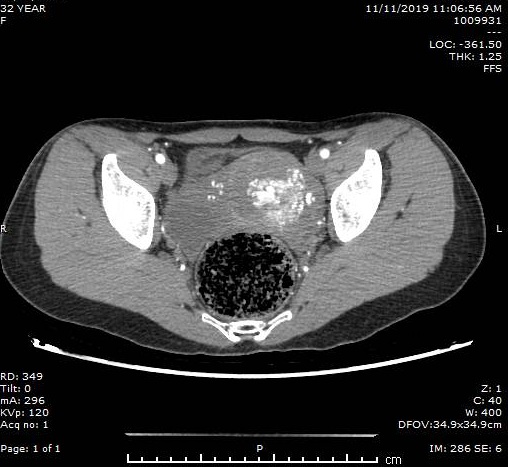

Trường hợp bệnh nhân Bàn Thị Huyền (32 tuổi, trú tại Bắc Giang) có tiền sử nạo hút thai cách đây 5 tháng, nhập viện ngày 09/11/2019 vào khoa phụ sản Bệnh viện Bãi cháy trong tình trạng ra máu âm đạo nhiều, đau bụng hạ vị. Kết quả thăm khám lâm sàng và làm các xét nghiệm cận lâm sàng (siêu âm, chụp CT scanner…) cho thấy trong buồng và cơ tử cung lệch trái có khối thông động tĩnh mạch kích thước khoảng 41x55mm.

Hình ảnh chụp CT khối thông động tĩnh mạch tử cung